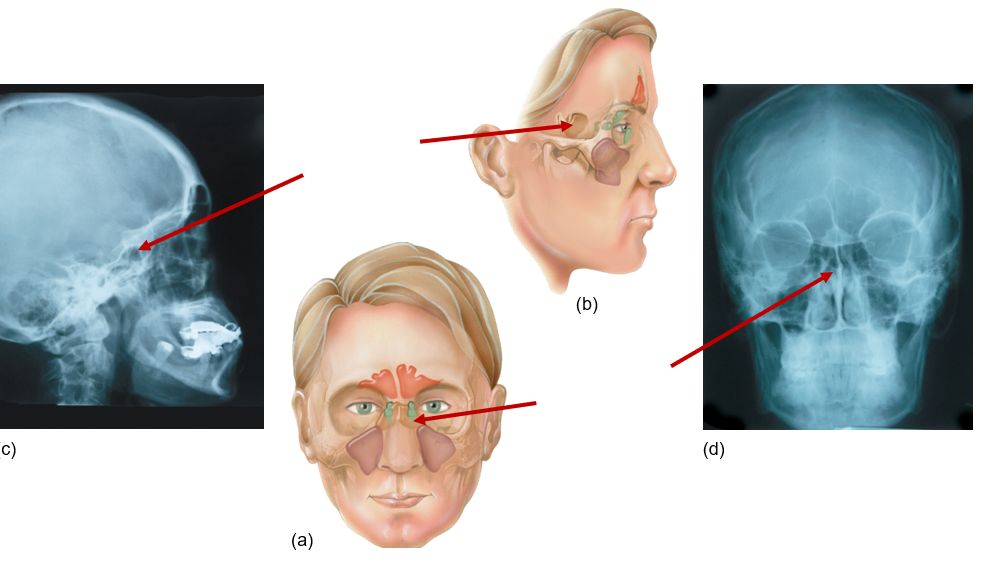

Frontal sinus

Front of head, above eyes

Sphenoid sinus

Behind eyes, near temples

Ethmoid sinus

Between eyes

Maxillary sinus

Next to nose, under eyes, maxilla